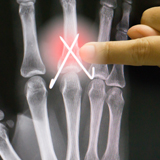

Choosing the right hand Therapist starts with them being able to read your X-rays and then fabricate the right brace for you. The therapists at Action Rehab Hand Therapy Clinic are experienced in assessing and reading X-rays.

Our therapists do regular GP and Emergency Doctor training and can advise on the most appropriate action for your Fractured Finger treatment.